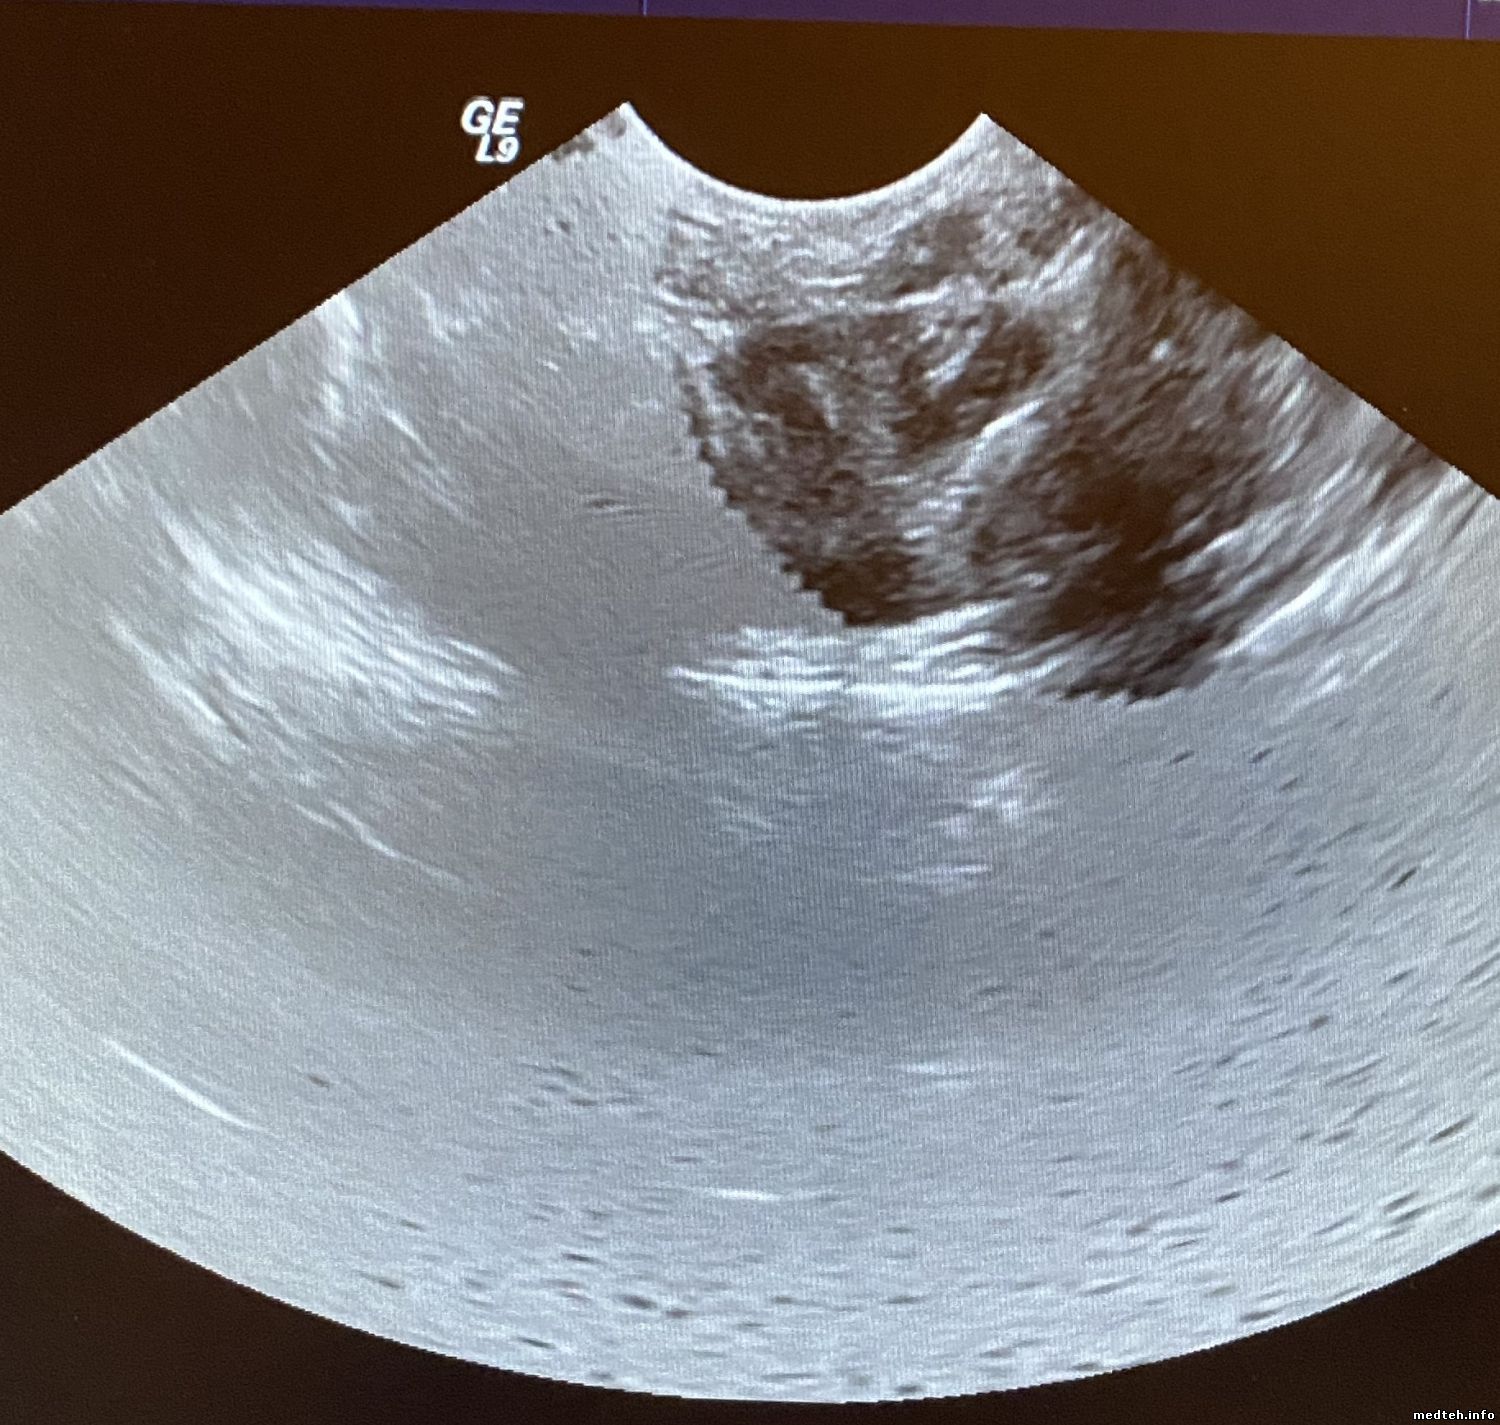

У меня по изображении Logiq 9 BT 3 появился атрефакт - на картинках. виден разной формы на всех датчиках...

боковой - круг на вагинальном, центральный конус на линейке, на конвексе ...

На вагинальном - http://www.medteh.info/_fr/52/9621642.jpg